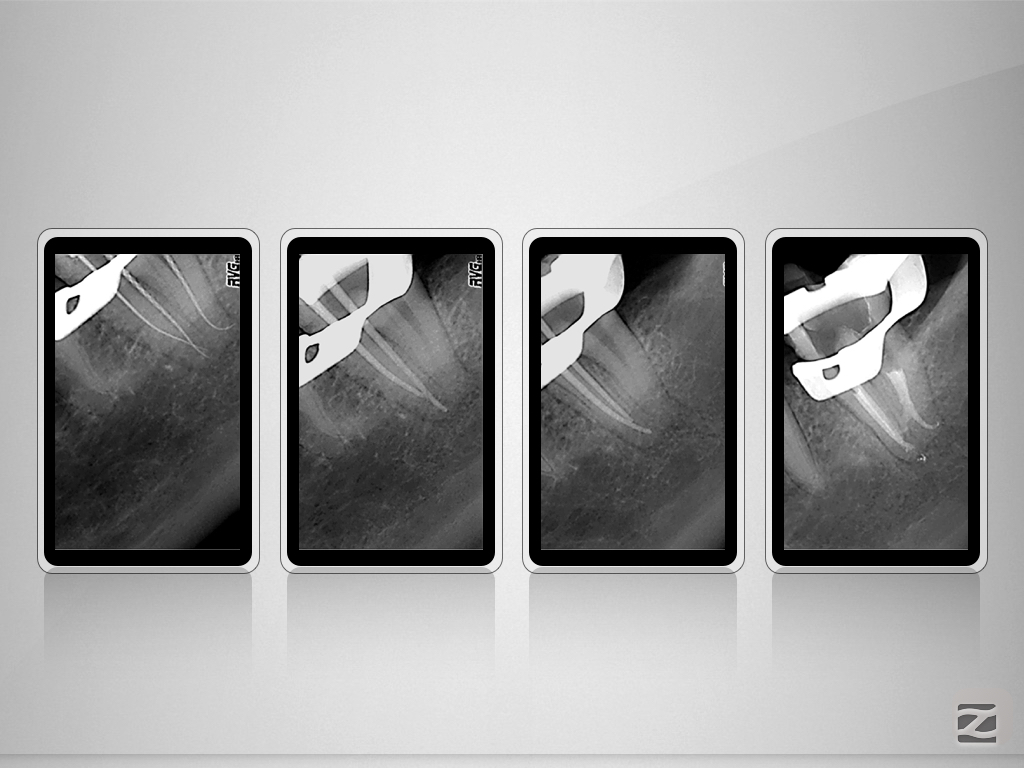

37D.003

X-Bein mit Kommunikation